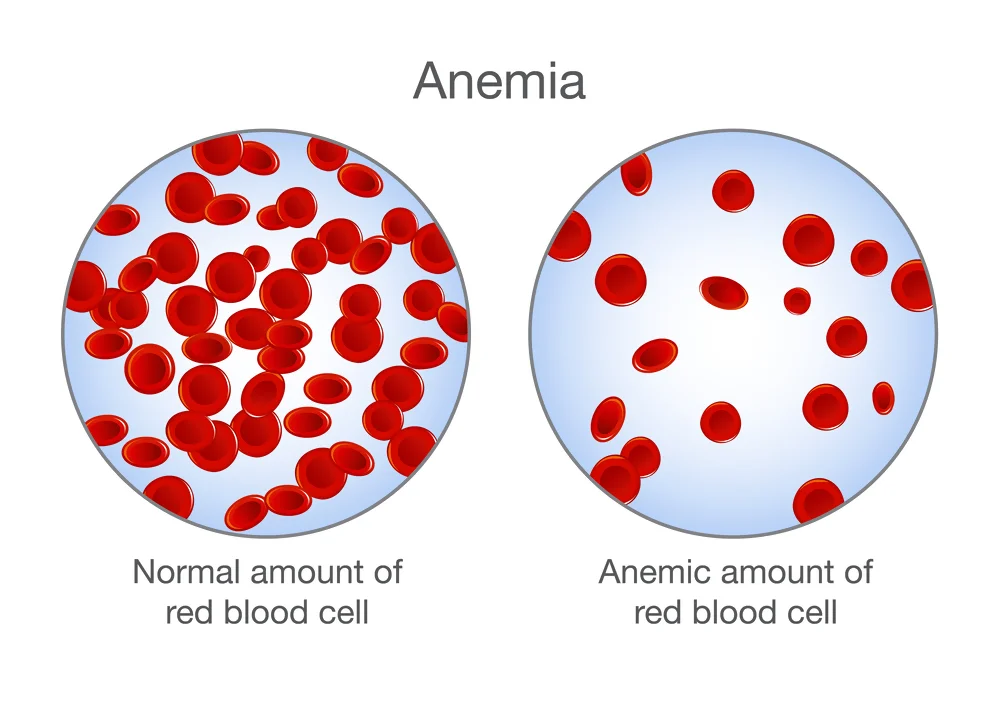

- Anemia • Georgetown • Naturopath • Natural Health Clinic of Halton (March 19, 2017)